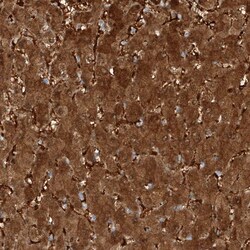

| Immunohistochemistry (Paraffin), Western Blot, Immunocytochemistry | |